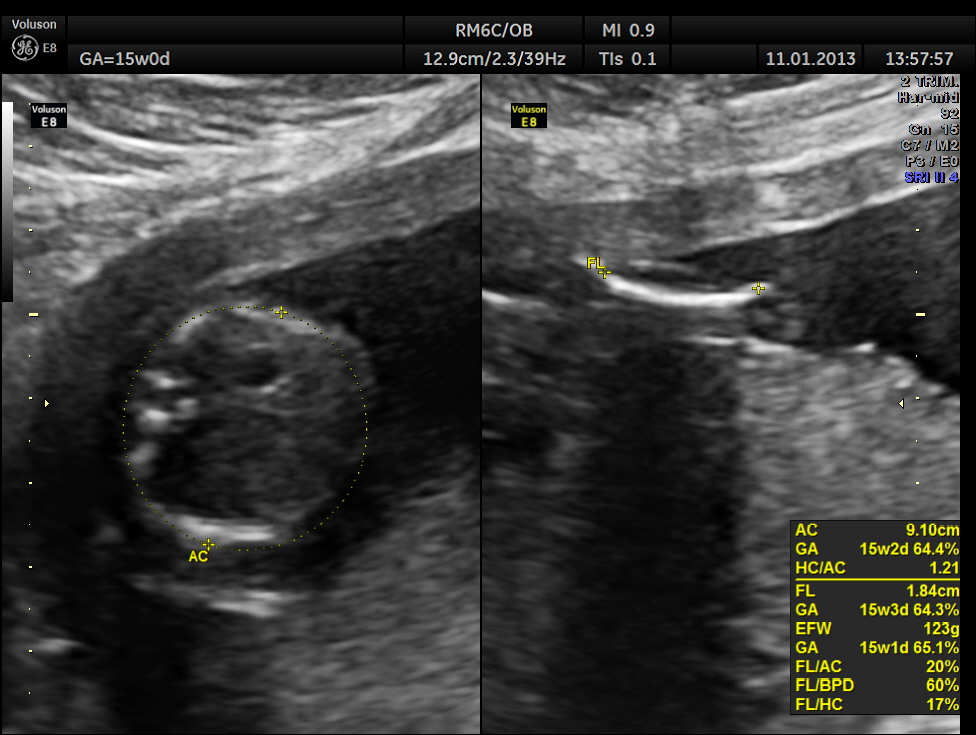

This was a 28 year old lady , primi gravida , who presented with acute lower abdominal pain . Her gestational age was around 15 to 16 weeks.

The pregnancy scan was otherwise normal.

So this patient was taken up for surgery because of the clinical presentation of acute pain , probably torsion. The mass lesion was removed and the pathologist reported it as PARA OVARIAN FIBROMA . The pregnancy was continued normally and was uneventful . The fetus showed mild bilateral pelvi ectasis persistently from 28 weeks onwards till delivery. Scan done 1 month after delivery showed normal kidneys in the child.